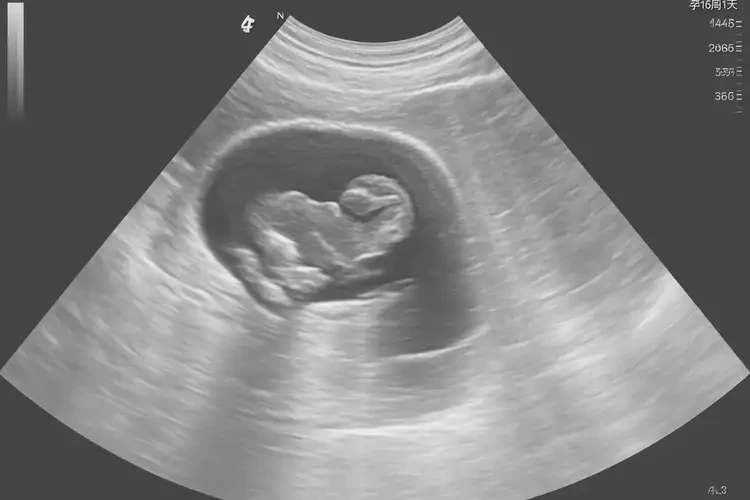

孕16周1天胎心率164寶寶還能要嗎

164次/分鐘的胎心率在孕16周1天屬于正常范圍,寶寶可以繼續(xù)妊娠。

胎心率是指胎兒心臟每分鐘跳動(dòng)的次數(shù),是評(píng)估胎兒健康狀況的重要指標(biāo)之一。在孕16周1天,胎兒的胎心率通常在140-170次/分鐘之間。164次/分鐘的胎心率在這個(gè)時(shí)間點(diǎn)是正常的,不需要過(guò)于擔(dān)心。

孕16周1天胎心率164寶寶還能要嗎(圖1)